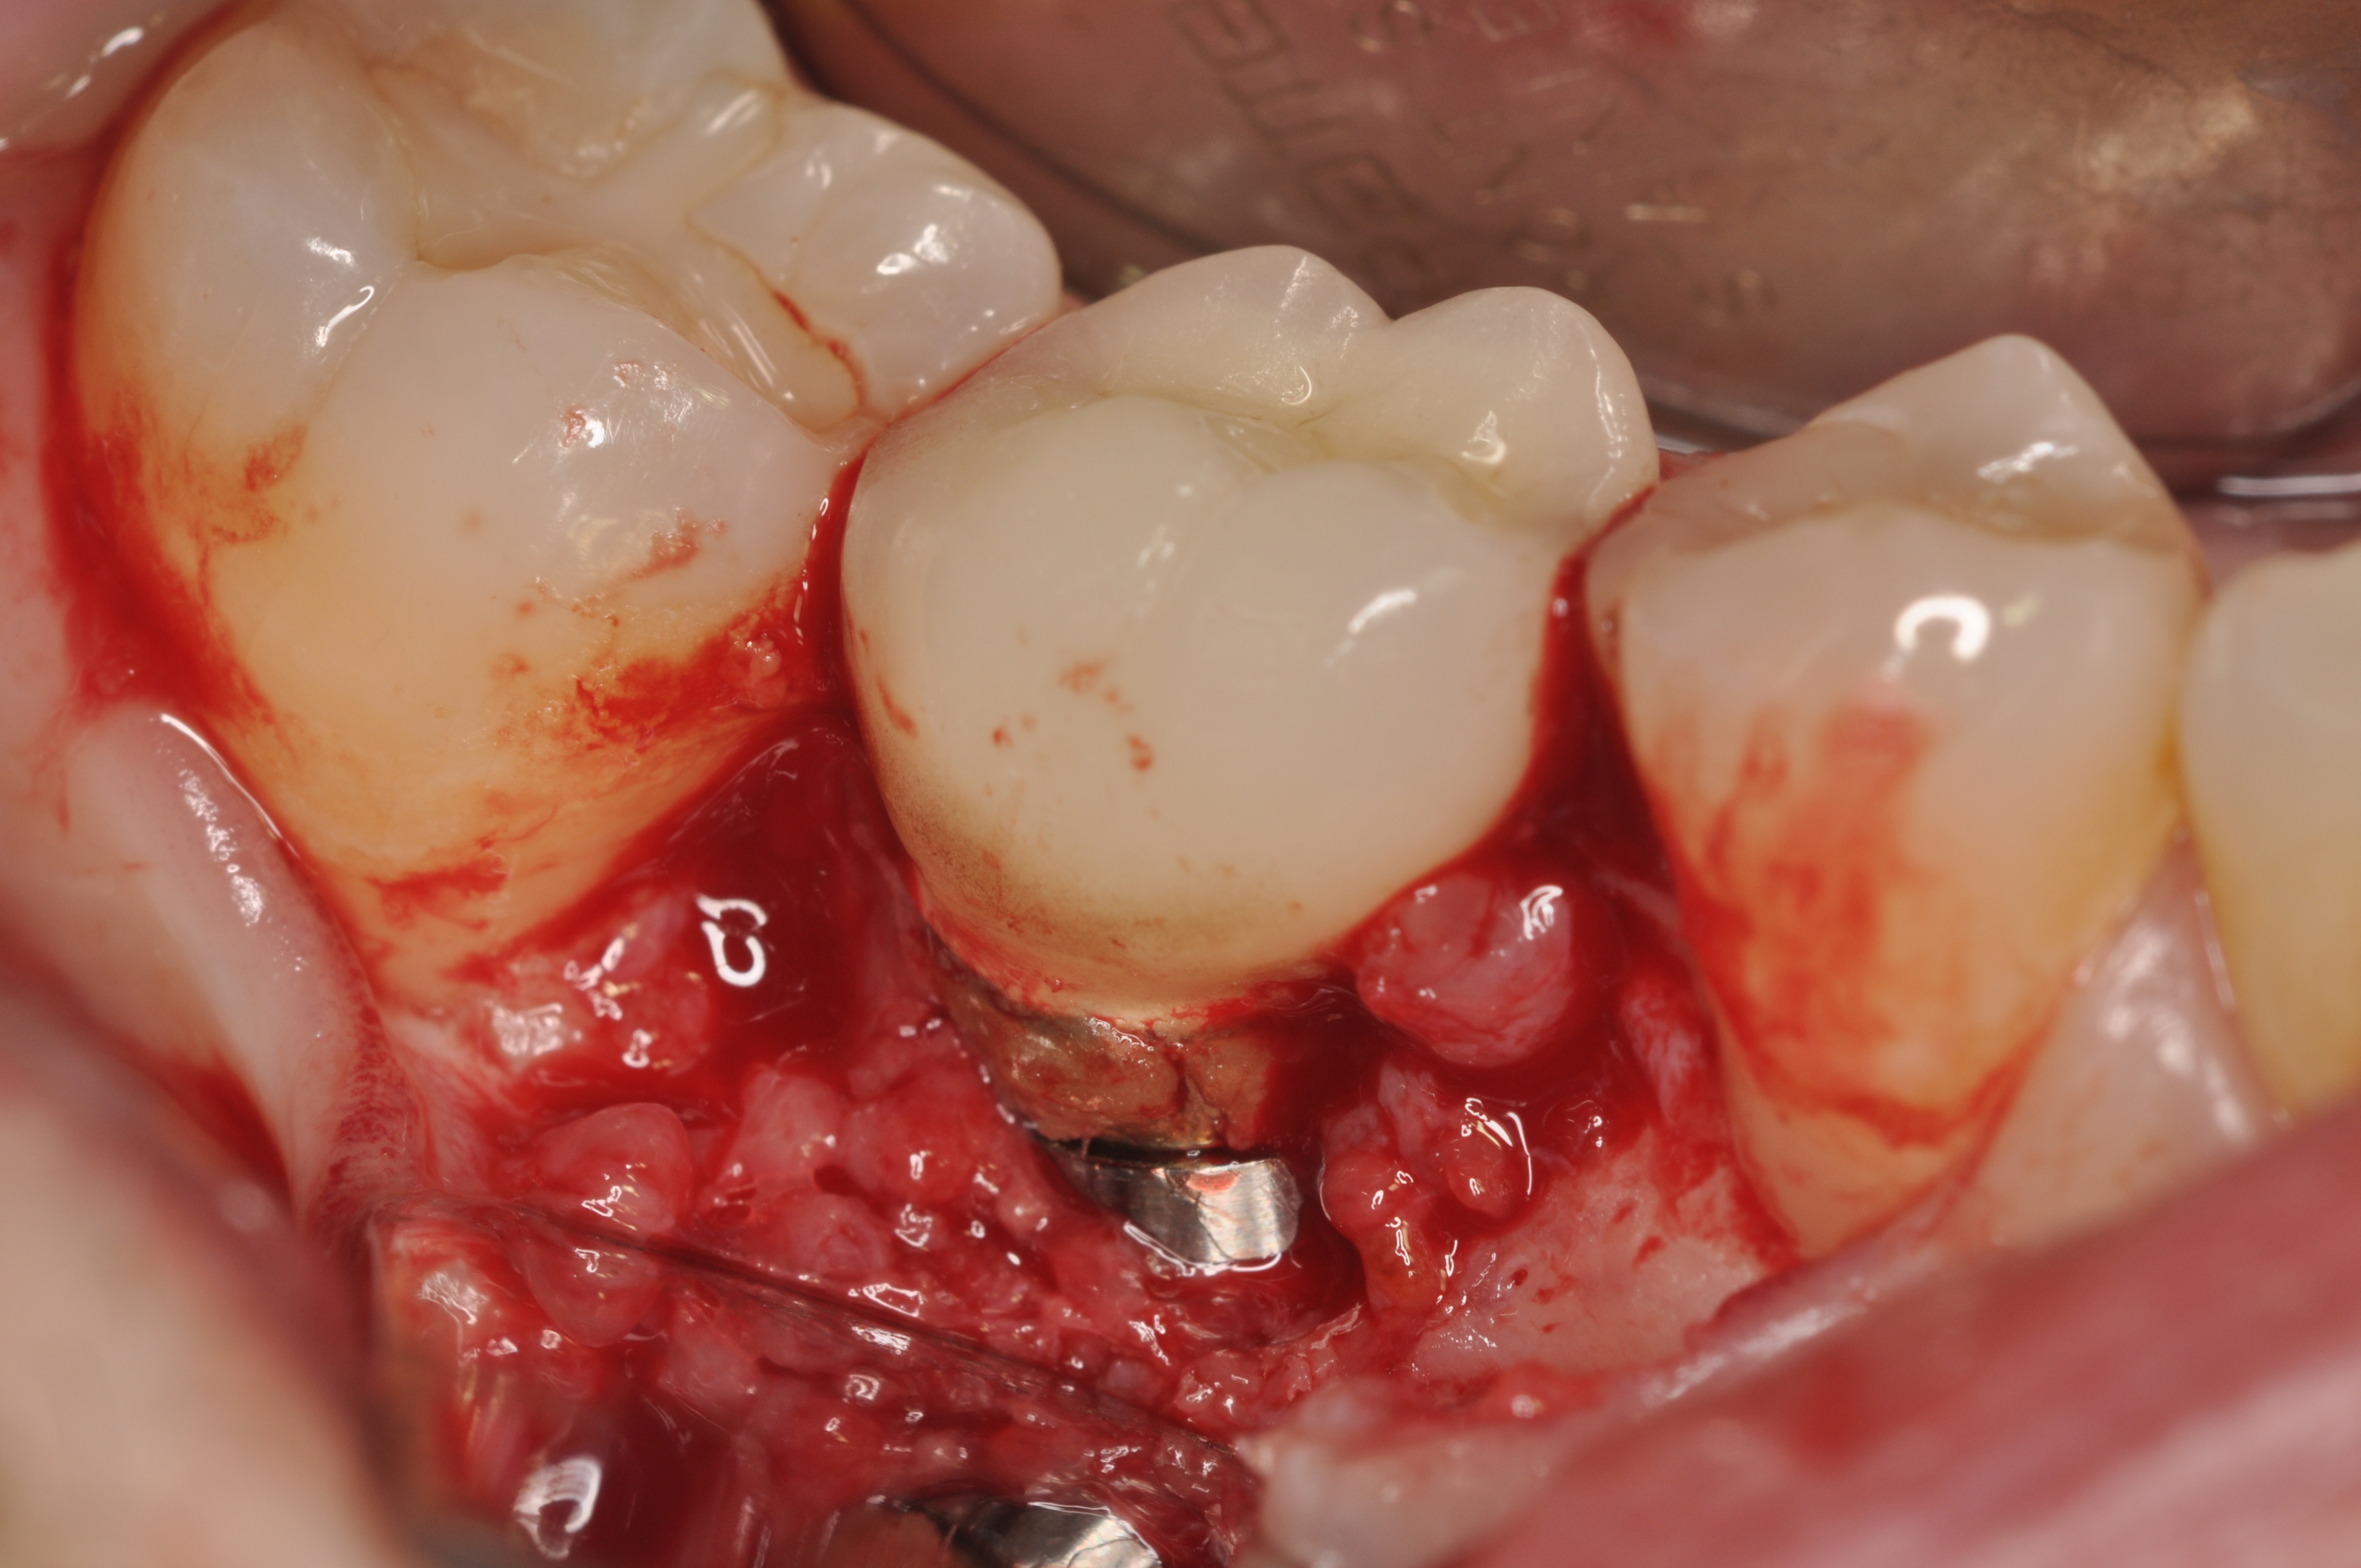

Fractured screws are challenging to retrieve, particularly when they are abutment screws. If the screw head is accessible, a hemostat can be used to remove it. However, when the screw breaks inside the implant (Figure 8 and Figure 9), removal can be highly complicated in order not to damage the implant’s internal threads. Therefore, many implant manufacturers have developed screw-retrieval kits. Because it is critical to be able to visualize the area, magnification using loupes and a surgical microscope may be necessary.8 Additional methods can be used to remove the fractured screw. A ¼ round bur set on a high speed can be used by lightly activating it, touching only the side of the screw. After repeating this technique several times, the screw may be able to be backed out with an explorer tip. Ultrasonic tips with copious irrigation may also dislodge the screw.7,20 In cases in which this fails, a small slot can be made in the head of the screw to back it out.21 If screw threads have been damaged during retrieval, they may be retapped using a tool obtained only from the implant manufacturer.7

Fig 8. Loss of restoration and subsequent tissue overgrowth from broken abutment screw as shown in the radiograph (Fig 9).

Figure 8

Fig 9. Radiograph depicting fractured screw inside of the implant.

Figure 9